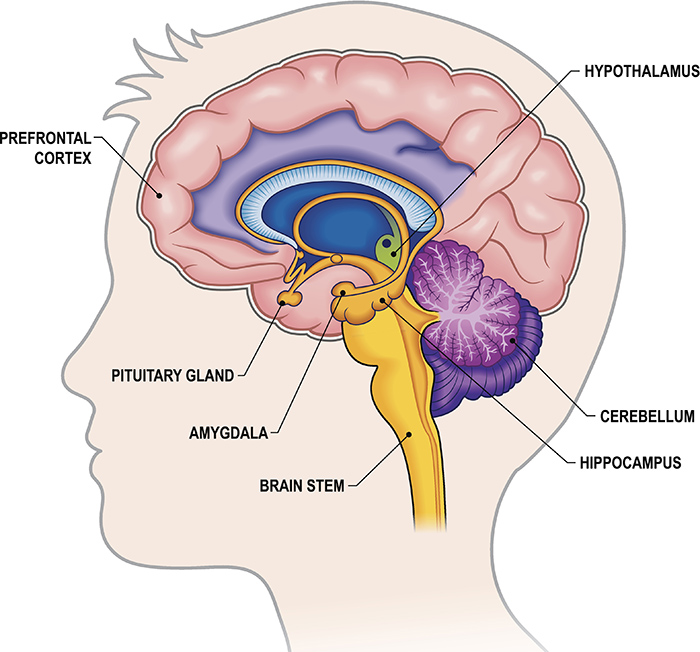

Amygdala: What It Is and What It Controls

Know Your Brain: Amygdala

Amygdala Function and Location

Amygdala's Location and Function

Amygdala: Anatomy, Location, and Function

Difference Between the Amygdala and the Prefrontal Cortex

The Cortex and the Amygdala - SOAR Library - SOAR

Schematic drawing illustrating the location of the amygdala and

The Limbic System